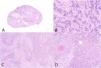

Histológicamente, se identificó una proliferación epitelial correspondiente a un carcinoma escamoso moderadamente diferenciado con presencia de remolinos córneos y perlas córneas, sin áreas de epidermis normal (fig. 1). Esta área mostraba un inmunofenotipo escamoso con positividad para p40, p63, CK AE1/AE3 y CK 5/6, mientras que SATB2 (fig. 2), actina y desmina fueron negativos; vimentina fue positiva en el componente osteoblástico y negativo en el escamoso.

En la transición con la zona descrita, se observó un área bien definida con otra morfología que mostró zonas de matriz eosinófila y otras basófilas con calcificaciones con aspecto de depósito de osteoide. En esta zona se observaron células grandes ocupando los espacios entre trabéculas y depósito de osteoide que, a nivel citológico, mostraron núcleos vesiculosos con nucléolo prominente y numerosas mitosis, algunas atípicas (fig. 1).

Estas células neoplásicas eran intensamente positivas para SATB2 nuclear y fueron negativas para CKAE1/AE3 (fig. 2), CK5/6, p40, p63, actina y desmina. Se realizó el diagnóstico de carcinoma escamoso moderadamente diferenciado con diferenciación a osteosarcoma de tipo osteoblástico. No se observó invasión linfovascular ni perineural.